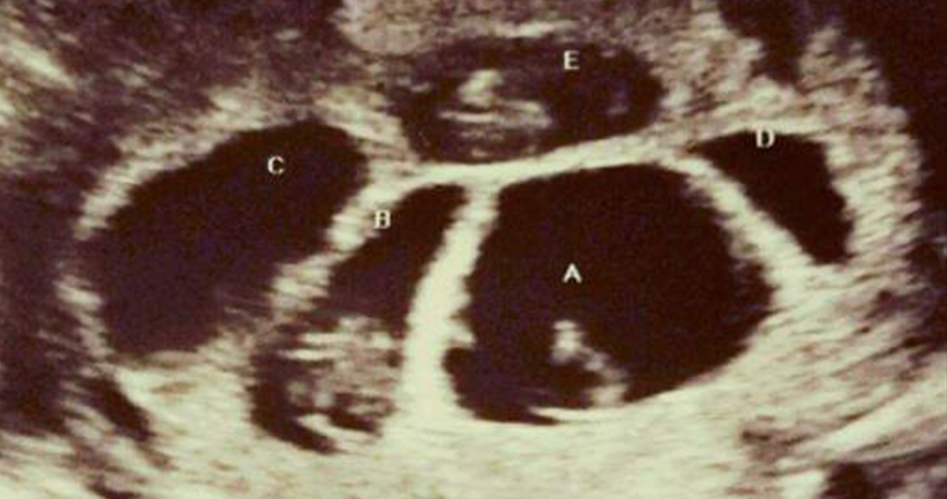

有些不 孕 症的夫妻為了生下孩子,會經歷許多辛苦的過程與磨難,有時候以為杳無希望,其實